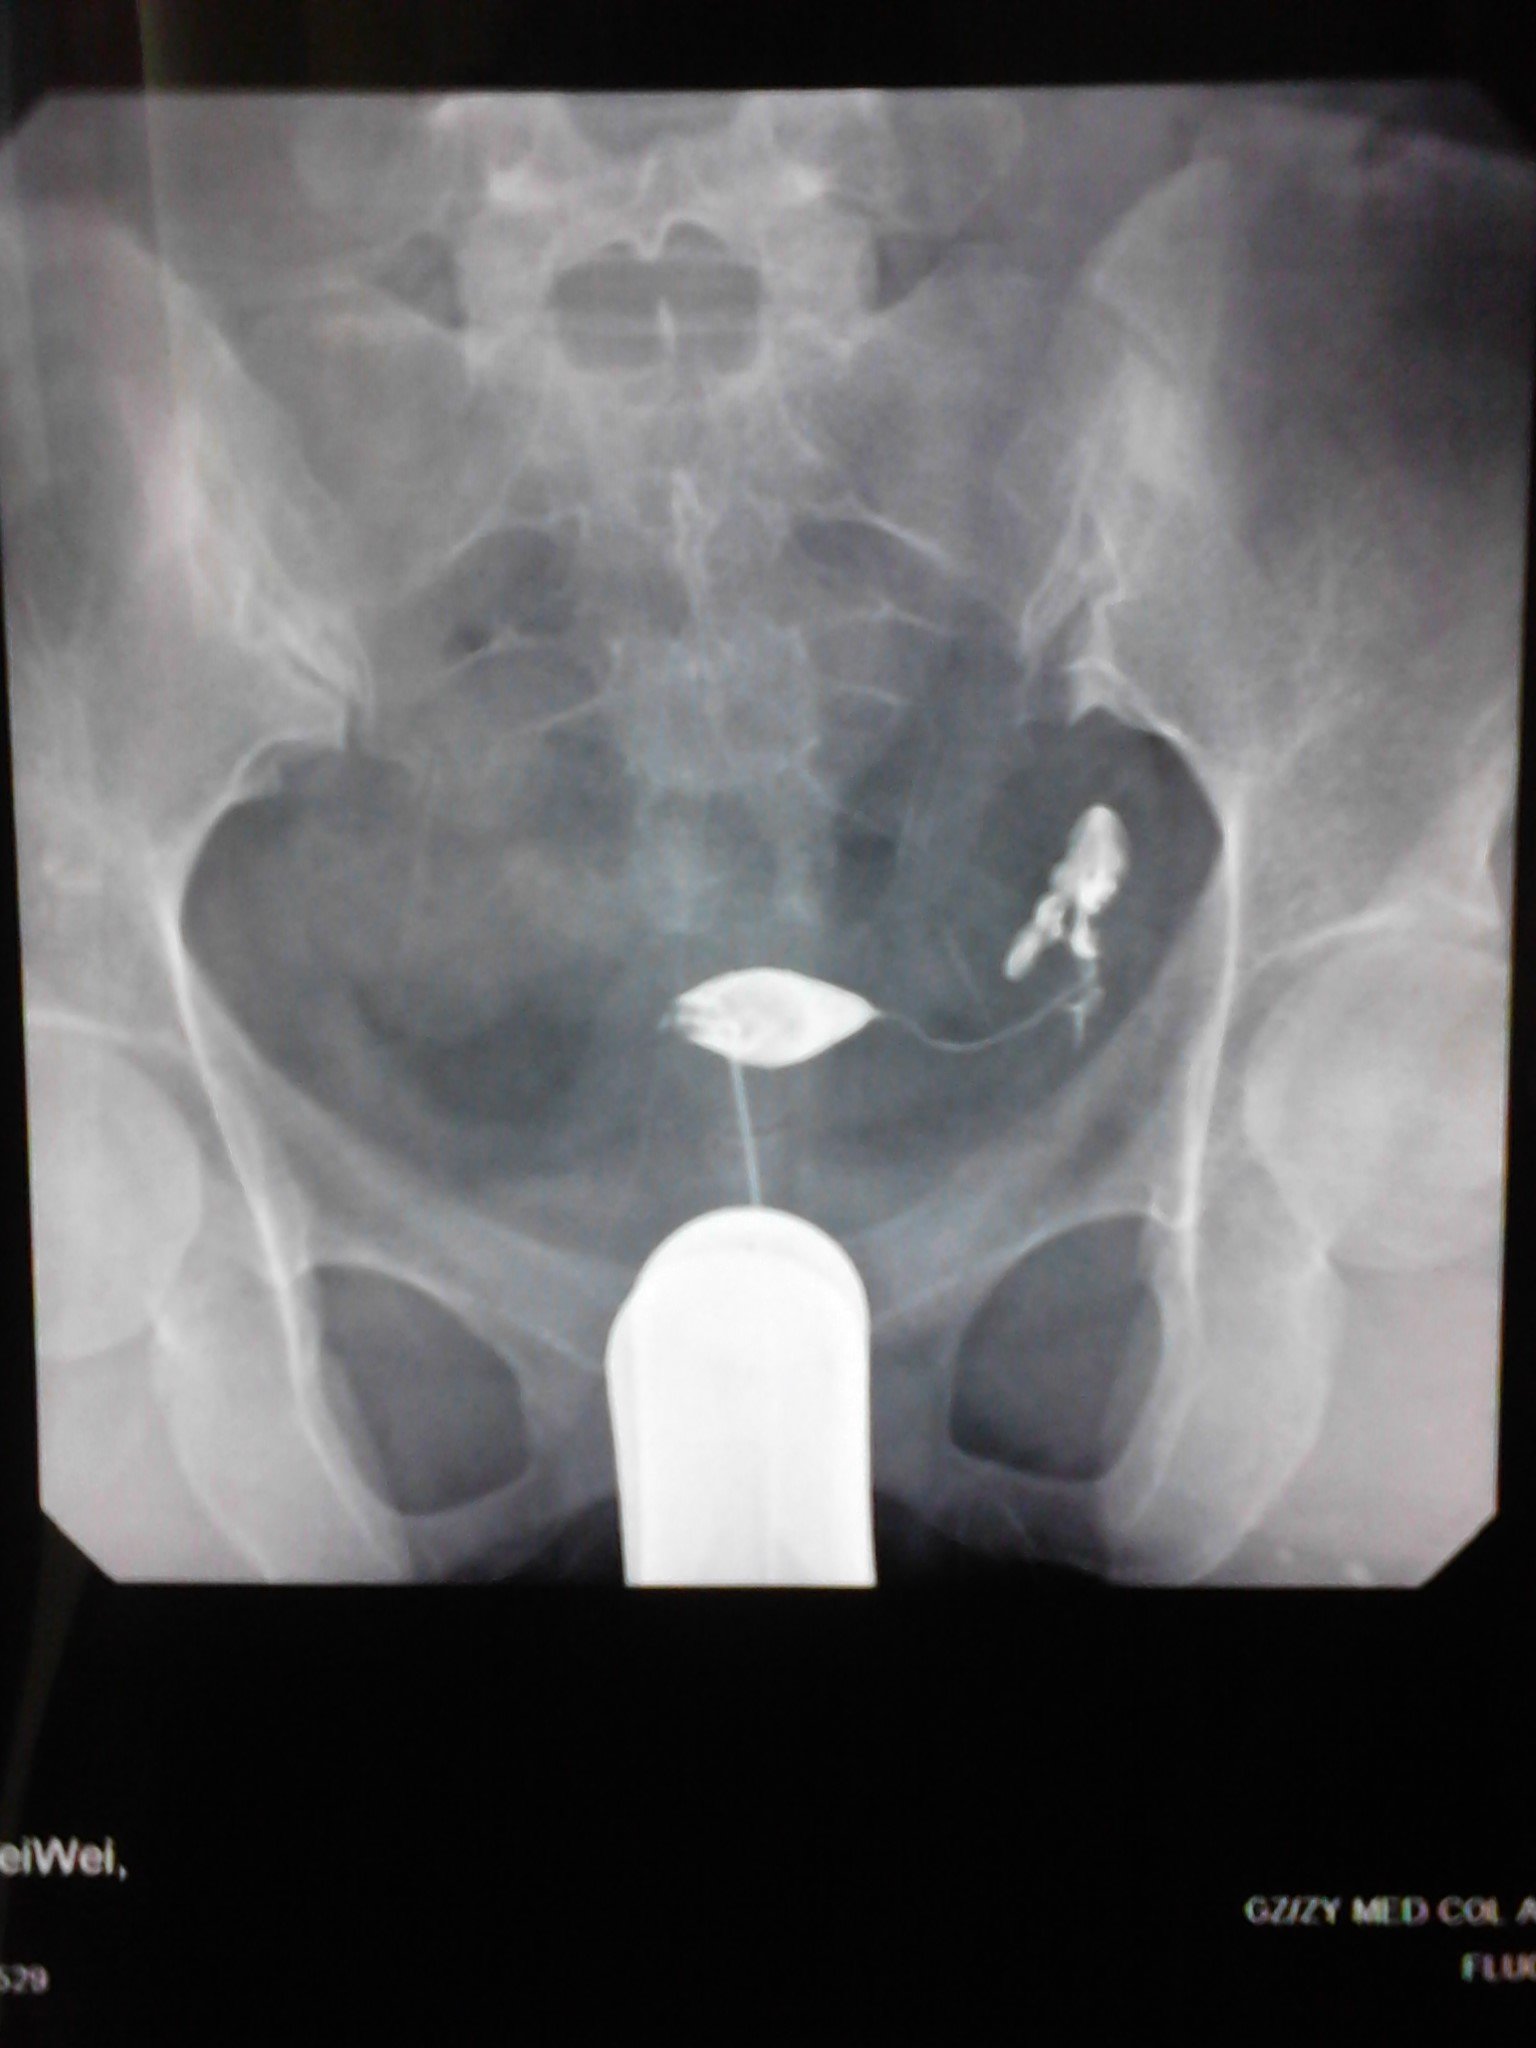

患者信息:女 25岁 贵州 遵义 病情描述(发病时间、主要症状等):子宫腔大小.形态无明显异常.子宫粘膜面光滑整齐.宫腔内见气囊及气泡所致充盈缺损。双侧输卵管全程显影.双壶腹部粘膜皱襞增粗.双侧伞端呈锥状.其内造影剂呈喷射状进入腹腔.进入腹腔之造影剂弥散欠佳曾经治疗情况及是否有过敏、 遗传病 史:现在正在吃中药